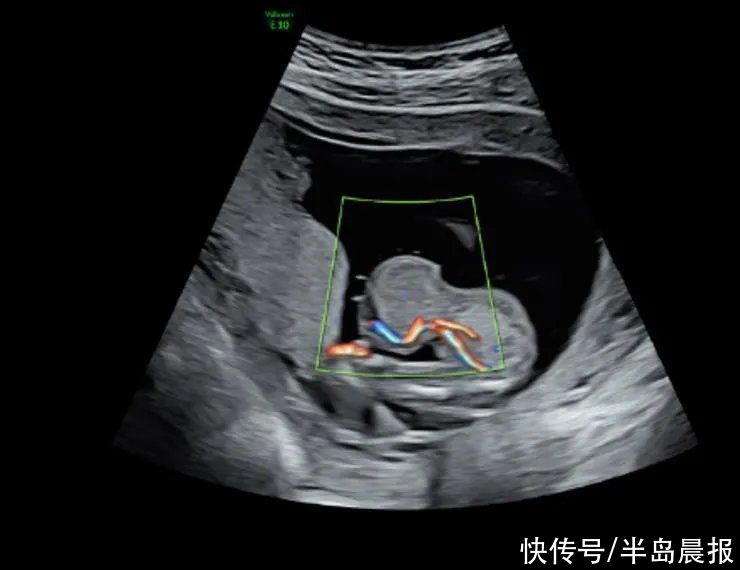

去年9月,黄女士历尽艰辛终于怀孕了。在她憧憬成为母亲的美好未来之时,超声筛查的结果却给了她当头一棒:III级超声检查结果显示,胎儿脐膨出,突出物大小35毫米×36毫米×36毫米。

脐带腹部入口处低回声包块,13毫米×12毫米×12毫米,考虑胎儿脐膨出声像。

超声检查结果显示胎儿“脐膨出”,且内容物为肝脏,虽然膨出不算非常罕见的先天性畸形,但是如果肝脏跑出来了,就有可能是腹裂了,预后会差很多。

高羽主任的一番话给了黄女士信心,她选择继续在中山六院产检。孕27周时,超声显示,宝宝其他方面发育良好,但脐膨出的大小已经达到45毫米×46毫米×44毫米(约为成年人拳头大)。